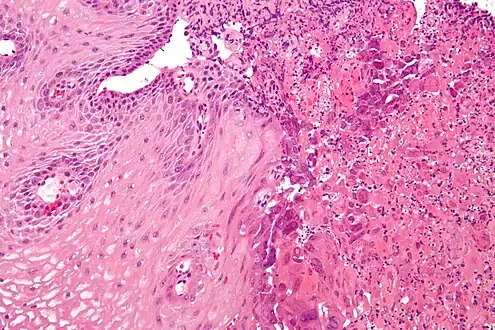

| An esophageal ulcer visualized by esophagoscopy: the reddened area at 10 o'clock on the surface of the mucosa. | |